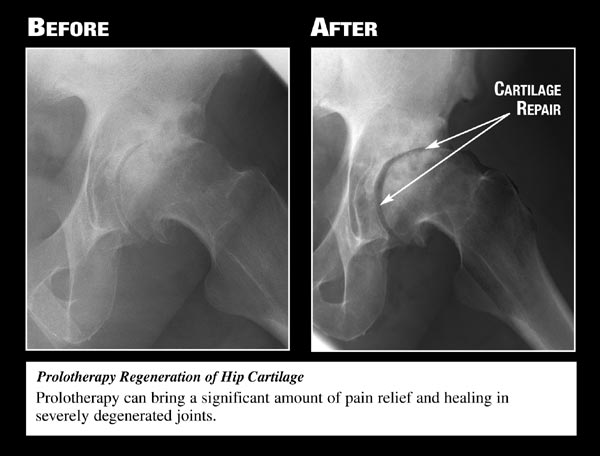

Used

with permission from Ross A Hauser, MD,

www.caringmedical.com.

Used with permission

from Ross A Hauser, MD,